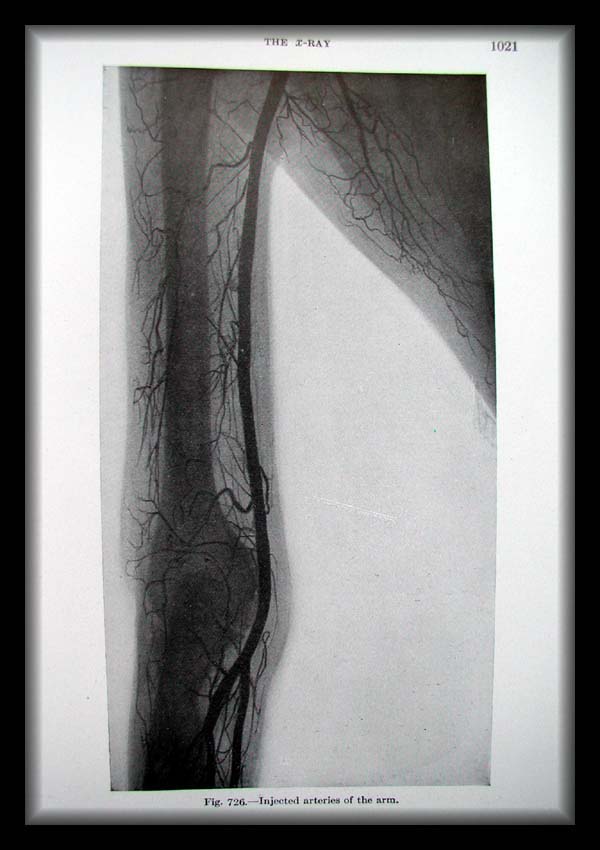

Page1021